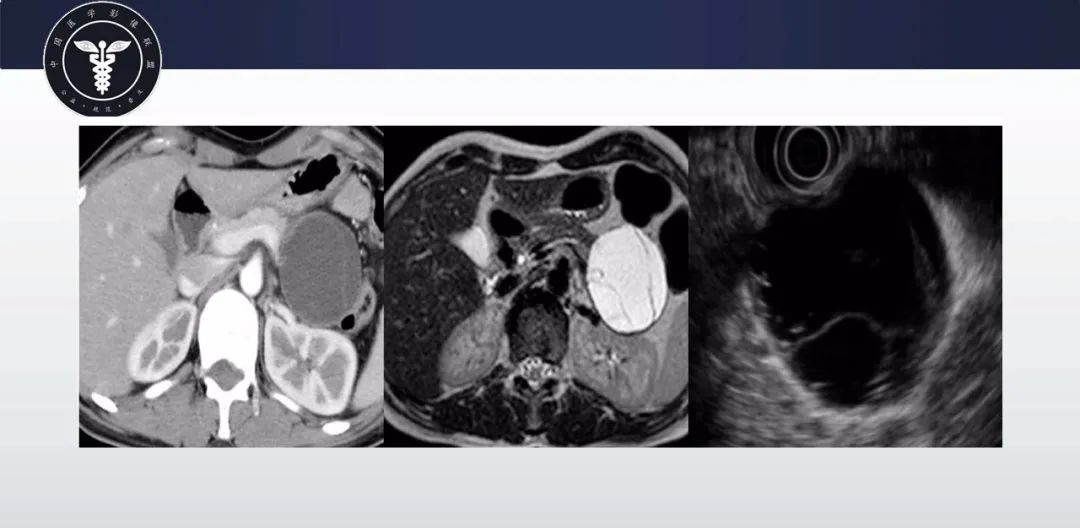

【病例】胰腺血管瘤1例CT及MR影像-2